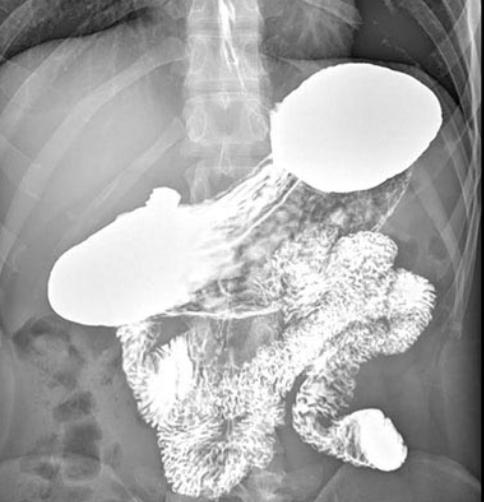

Il paziente ingerisce un liquido contenente solfato di bario (radiopaco), che riveste le pareti esofagee e permette di visualizzarle ai raggi X.

Si eseguono radiografie statiche e fluoroscopia dinamica per osservare il passaggio del contrasto attraverso l’esofago fino allo stomaco.

📌 Reflusso gastroesofageo (GERD) → Visualizzazione del contrasto che risale dallo stomaco nell’esofago.

📌 Acalasia → Dilatazione dell’esofago con segno a becco di uccello.

📌 Stenosi esofagea → Restringimenti o aree di ostruzione.

📌 Diverticoli esofagei → Pouch o estroflessioni della parete esofagea.

📌 Ernia iatale → Dislocazione dello stomaco attraverso il diaframma.

📌 Spasmo esofageo diffuso → Contrazioni irregolari e non coordinate dell’esofago.